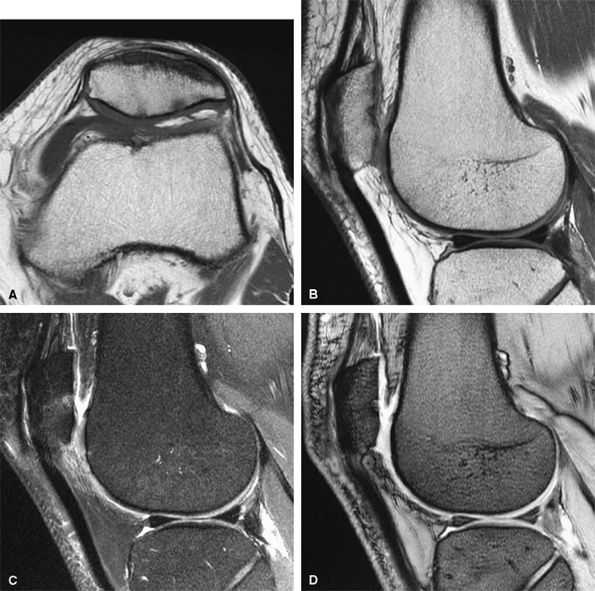

FIGURE 1.1 ● Routine knee examination. (A) Axial T1-weighted 2D fast/turbo spin-echo image. (B) Sagittal proton density-weighted image. (C) Sagittal proton density-weighted image with chemical fat suppression. (D) Gradient-echo image.